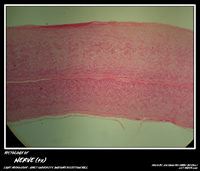

NERVE TISSUE